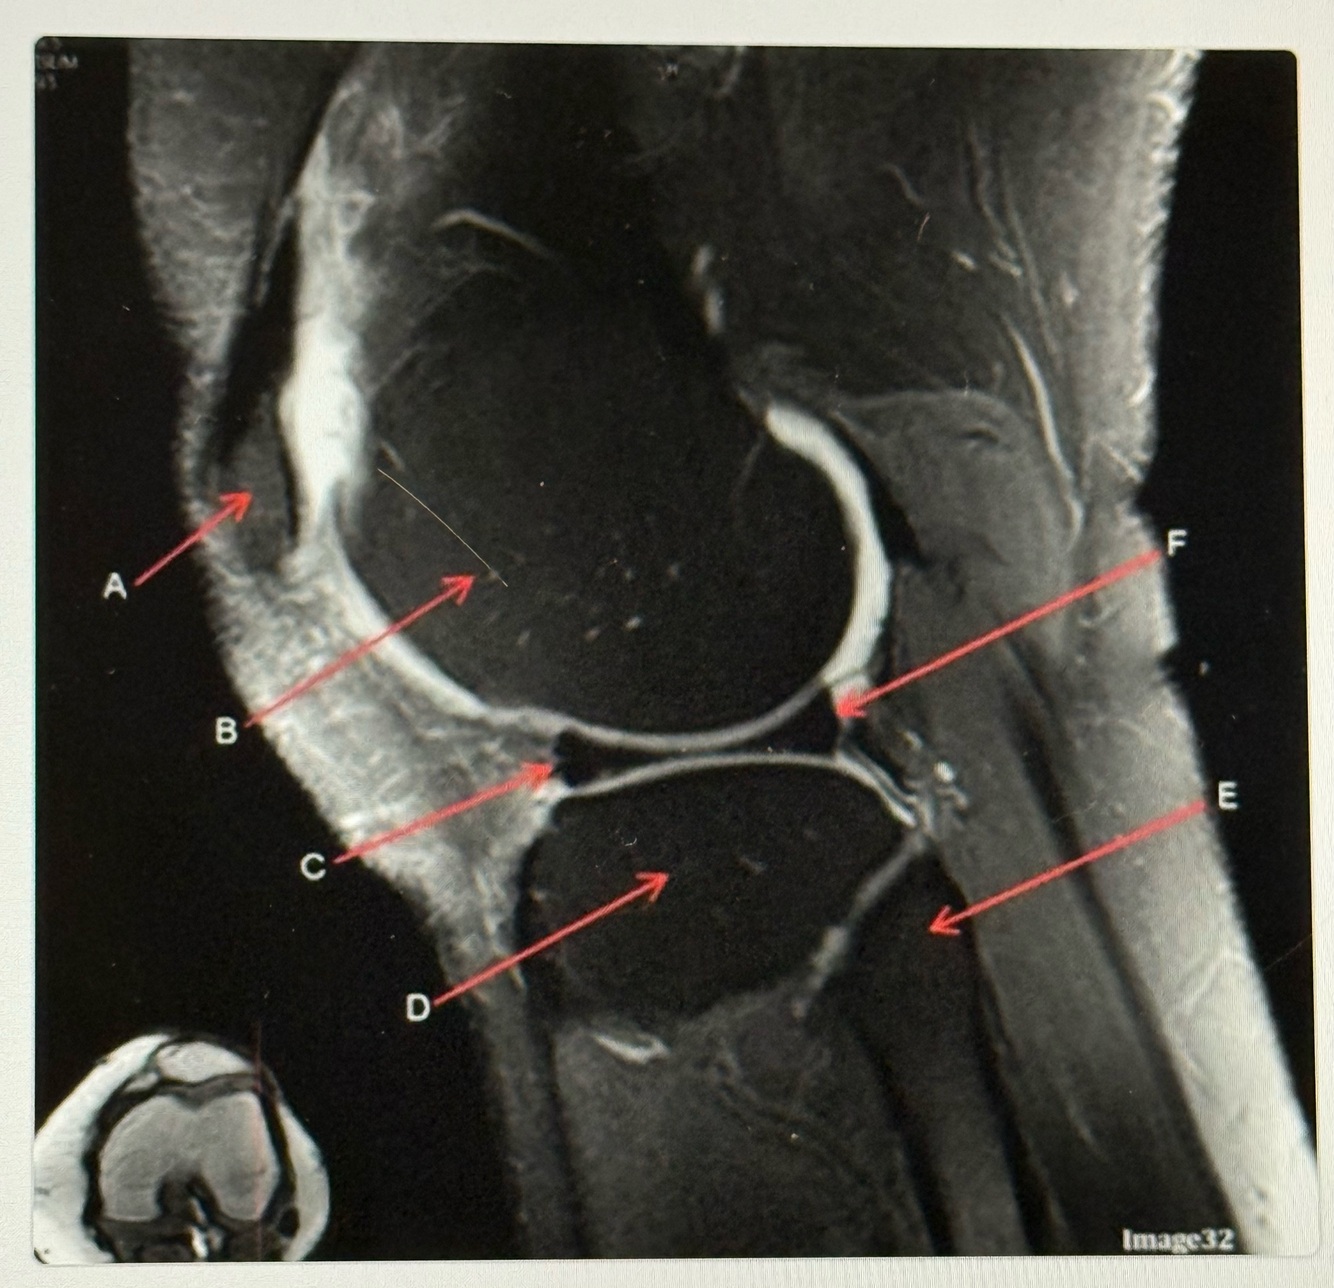

Q

Letter C points to the

A

Patellar tendon

17

Letter D points to the

Tibia

18

Letter E points to the

Posterior cruciate ligament (PCL)

19

Letter F points to the

Femur